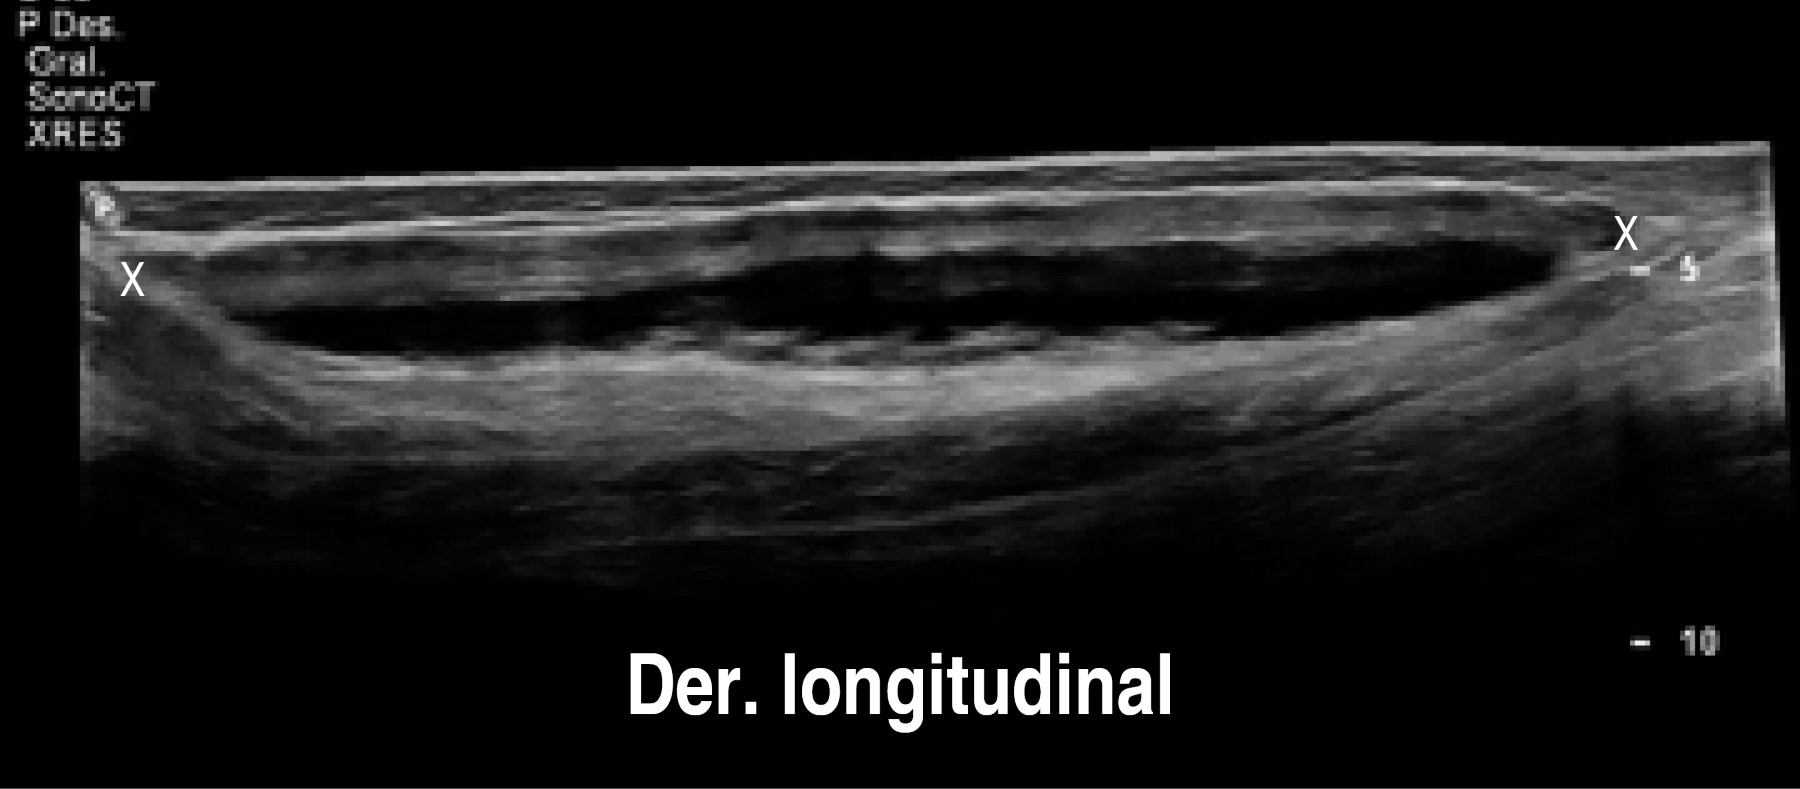

En el estudio de ultrasonido se encontró extensa colección líquida intracapsular de la pierna izquierda, sin descartar la ruptura del implante. El implante derecho con datos de ruptura y mínima colección.

Procedimiento quirúrgico (Figuras 1, 2, 3, 4 y 5):

El 24 de octubre se llevó a cabo el retiro del implante de la pantorrilla izquierda bajo anestesia local y sedación. El retiro del implante derecho se difiere para otro tiempo quirúrgico (dos meses) a petición de la paciente para que se facilitara su movilidad en el postoperatorio. En la imagen preoperatoria observamos el aumento de volumen de la pierna izquierda (Figura 6).